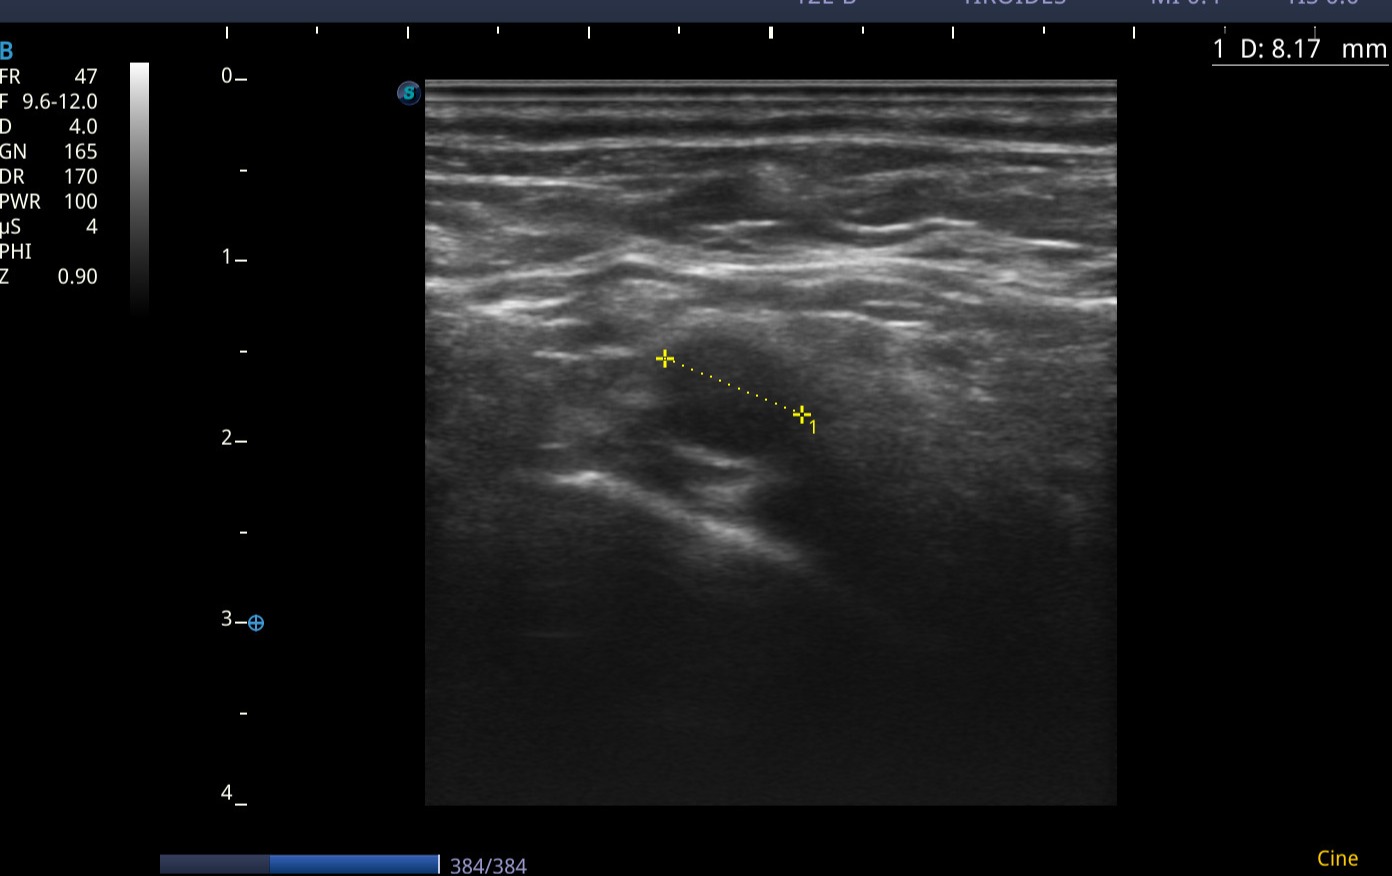

En las imágenes ecográficas del centro de salud se visualizan los siguientes hallazgos:

Conglomerado adenopático en cadena ganglionar laterocervical izquierda. Los ganglios visualizados presentan márgenes poco definidos/irregulares, ausencia de hilio ecogénico, ecogenicidad heterogénea, y algunos con forma redondeada, características con alta sospecha de malignidad. Dadas tales características y antecedentes personales, se deriva de forma preferente a Medicina Interna, para completar estudio de adenopatías.